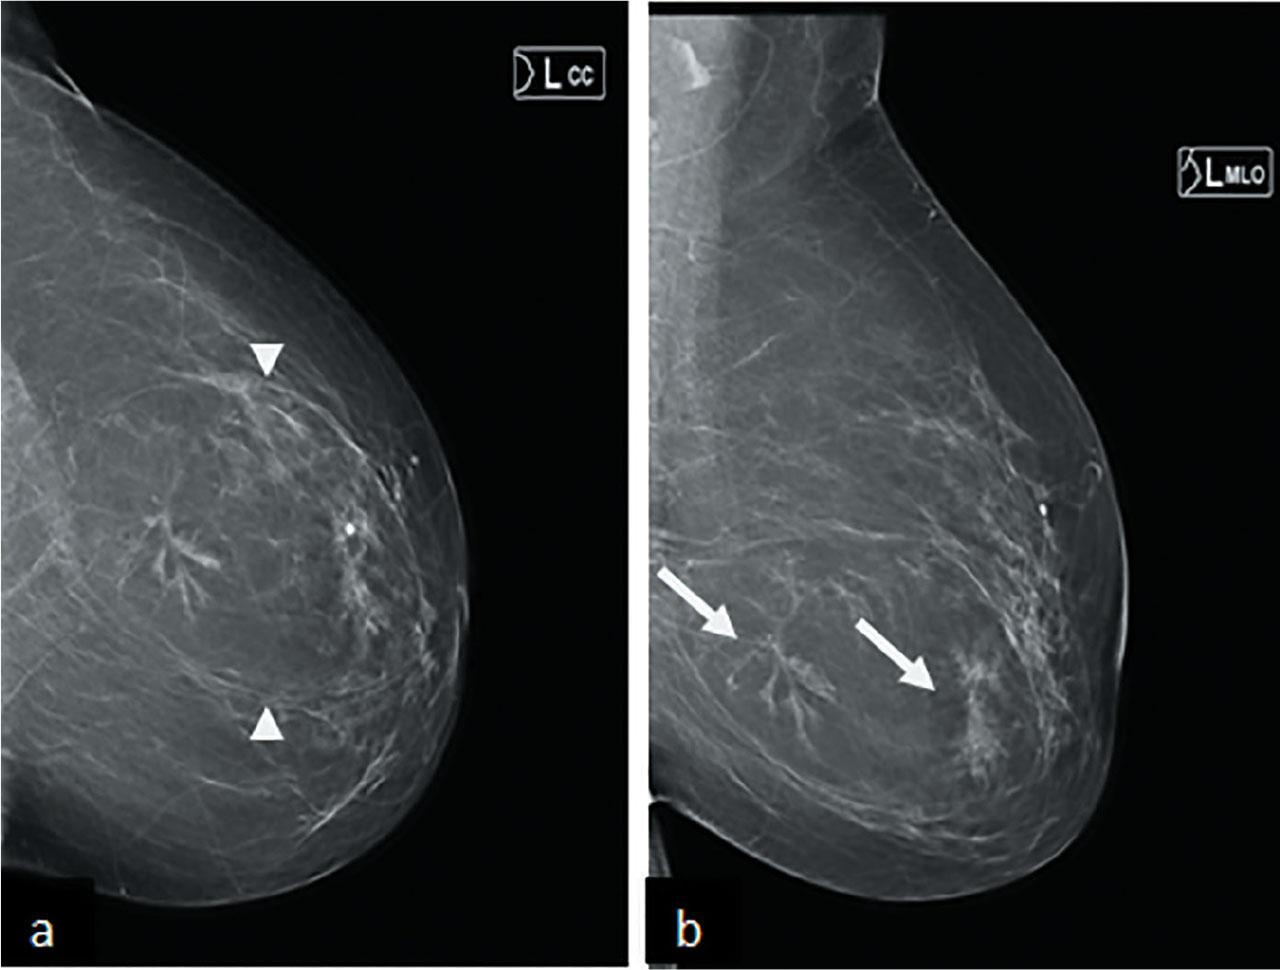

A 61 year old woman was recalled for assessment after a screening mammogram. She was known to have long standing benign lump in her left breast which had shown interval development of central distortion. On clinical palpation, there was mobile mass in left breast. Digital breast tomosynthesis was performed which confirmed the presence of architectural distortion (Figure 3a&b). Ultrasound showed an oval encapsulated mass running parallel to the skin with central hypoechoic areas (Figure 4a&b). The central distortion and corresponding hypoechoic change was suspicious, therefore 14G US guided core biopsy was performed.

(a) CC and (b) MLO views of mammogram, showing circumscribed mass with pseudocapsule (arrow heads) and central area of distorsion (arrow) in the left lower central breast.